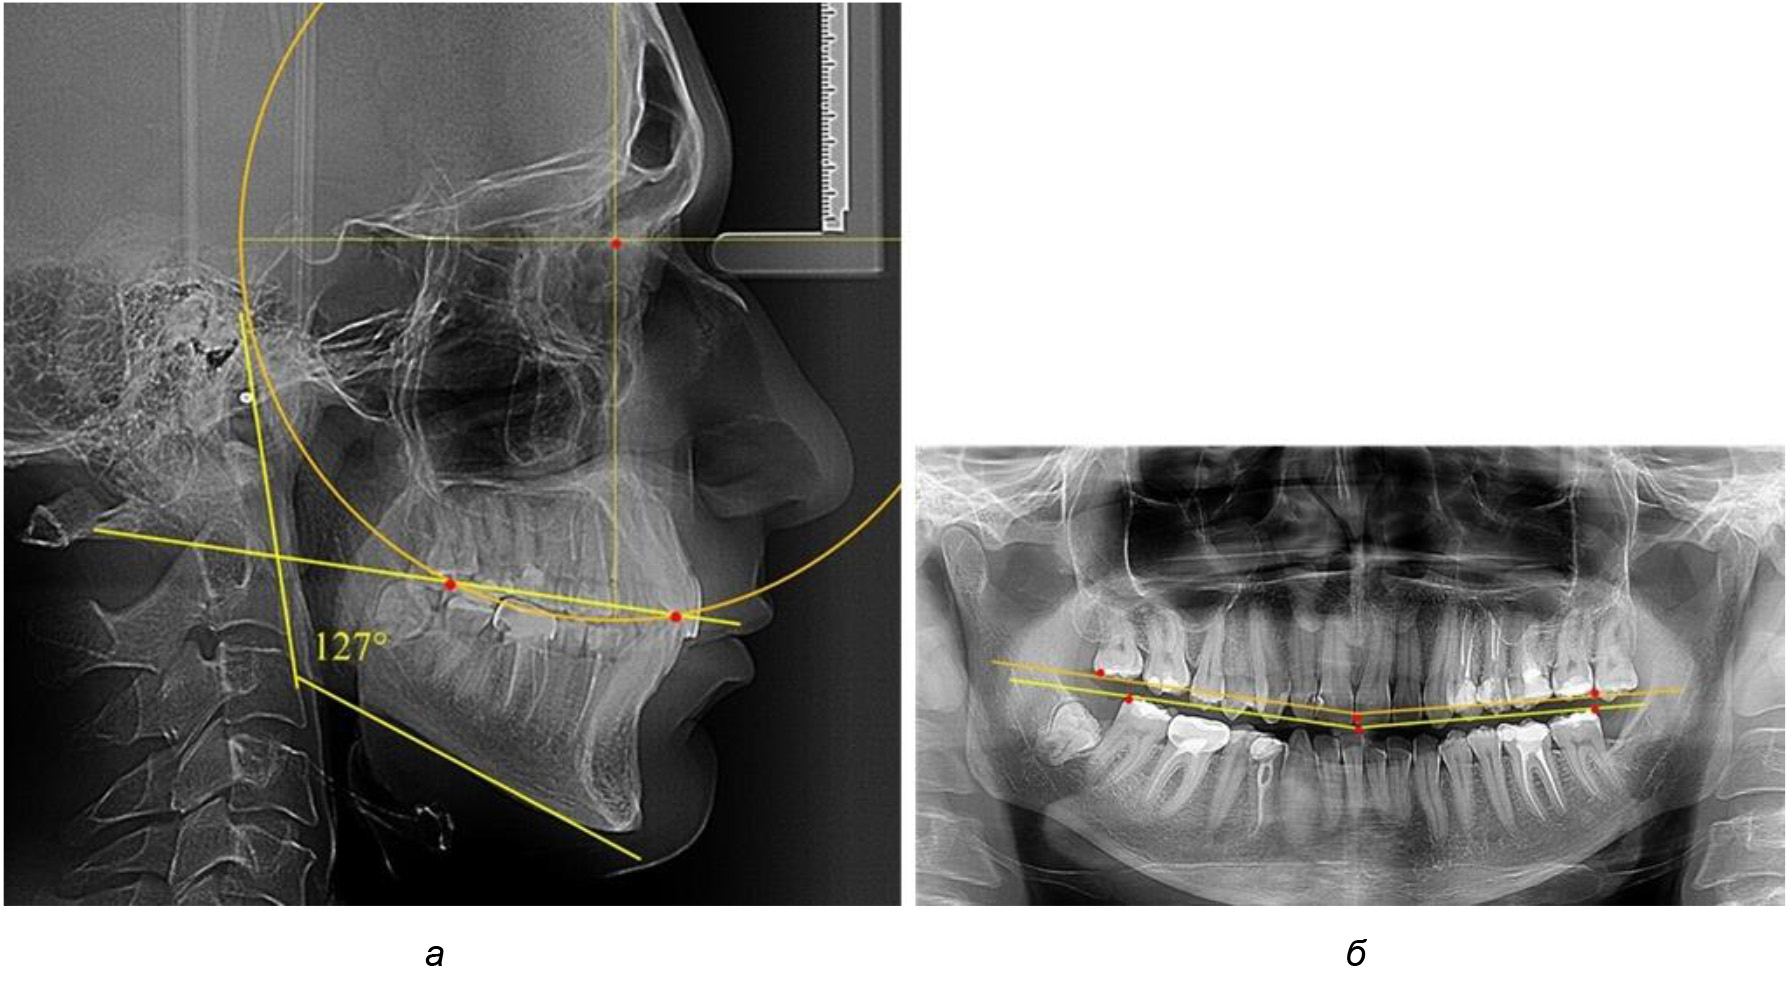

В 3-ю подгруппу вошли ТРГ и ОПТГ 14 человек 1-й группы, что составило (22,58 ± 5,31) % от общего количества людей 1-й группы. Величина угла нижней челюсти в среднем составила (114,85 ± 2,87)° и характеризовала горизонтальный тип нижней челюсти.

Глубина кривой Spee в среднем по 2-й подгруппе составил (2,94 ± 0,47) мм, что было меньше, чем в других подгруппах. Деление величины радиуса круга к длине окклюзионной линии составило 1,616 ± 0,02 (рис. 4).

Рис. 4. Особенности кривой Spee на ТРГ (а) и ОПТГ (б) у людей с горизонтальным типом лица

У людей с аномалиями окклюзии по сагиттали в 1-й подгруппе обследовано 9 человек. Обращает на себя внимание увеличение глубины кривой Spee, что нами расценивалось, как патологическая форма кривой линии окклюзии.

Глубина кривой Spee в среднем по 2-й подгруппе составила (5,69 ± 1,57) мм, что было достоверно больше, чем у людей с физиологической окклюзией (р ˂ 0,05). Достоверных различий с показателями, полученными при анализе ТРГ и ОПТГ, нами не отмечено (р ˃ 0,05). Отношение радиуса окружности к сагиттальному размеру окклюзионной линии в среднем по подгруппе составляло 1,372 ± 0,042 и не соответствовало числу Фибоначчи, что может быть использовано в качестве диагностического критерия определения патологической формы кривой Spee. После лечения пациентов техникой «прямой» дуги было отмечено незначительное увеличение сагиттального размера окклюзионной лини в среднем на (2,12 ± 0,77) мм. Однако окклюзионная линия практически касалась окклюзионного контура всех жевательных зубов, и отмечалось практически полное отсутствие кривой Spee.

Таким образом, проведенное лечение техникой «прямой» дуги способствует нормализации окклюзионного равновесия и торку передних зубов, однако не соответствует оптимальному окклюзионному статусу, характеризующему физиологическую окклюзию. При этом величина нижнечелюстного угла оставалась на прежнем уровне (рис. 5).

Рис. 5. Особенности ТРГ при патологической кривой Spee до лечения (а) и после лечения (б) техникой «прямой» дуги